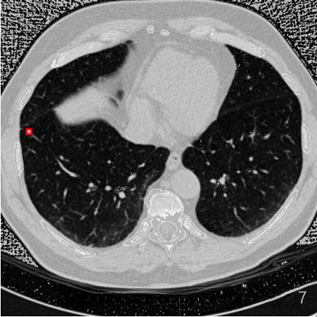

原图:

预测:

标注图(根据标注生成):

在应用yolov3算法进行肺结节检测时,发现其在实际应用中仍存在一定局限性。具体表现为:1)迭代训练不足导致模型尚未达到充分收敛的状态;2)有必要对训练数据集进行聚类分析以优化参数设置,并调整anchor框大小与比例参数设置以进一步提升检测精度。